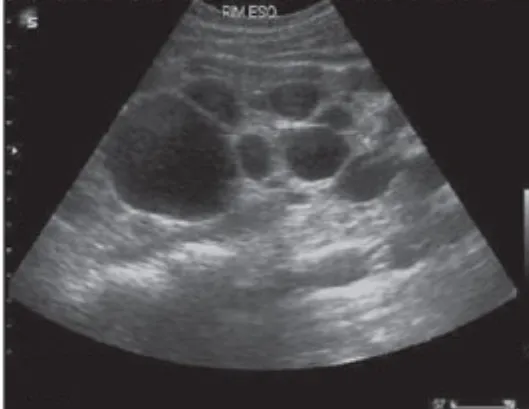

Injúria Renal Aguda (revisão Lancet 2025)